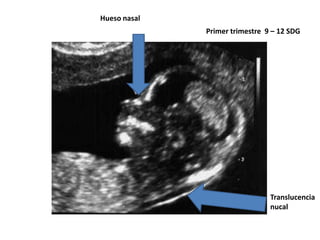

• USG:

 translucencia nucal

Hipoplasia del hueso nasal

Hueso nasal

Primer trimestre 9 – 12 SDG

Translucencia

nucal